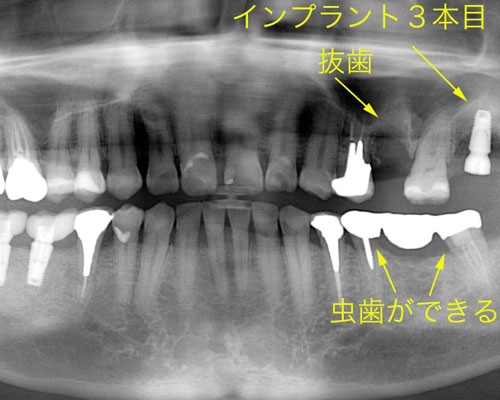

3本目のインプランと左下のブリッジに問題発生

やっと右下にセラミックの歯が入りました。左上にも3本目のインプラントを入れ、もう1本の割れた歯を抜きました。しかし、レントゲンをよく見てみると左側を酷使していた為か、ブリッジの下に虫歯ができて怪しくなっています。